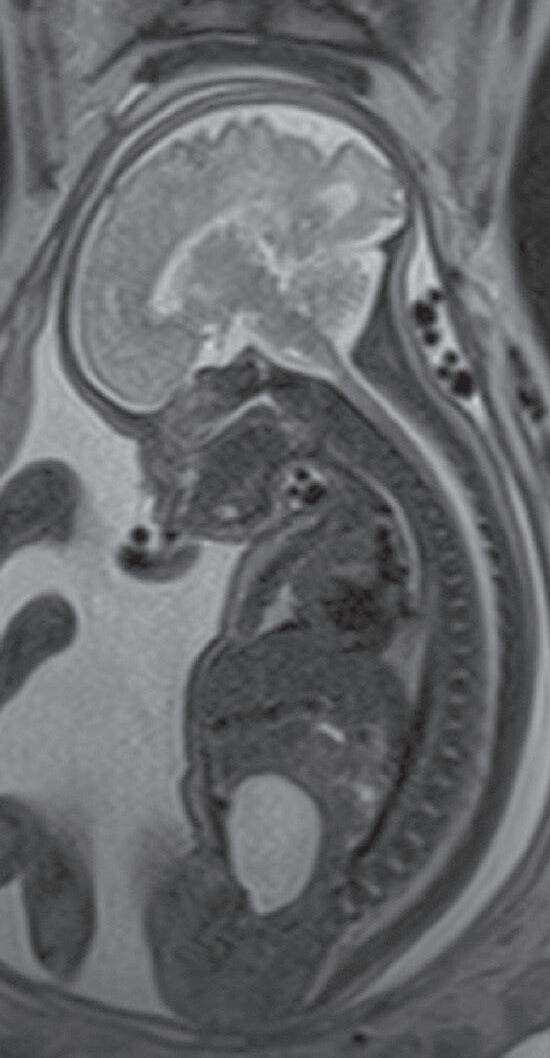

A perinatologia, também conhecida como medicina materno-fetal, é uma subespecialidade dedicada ao estudo, ao diagnóstico e ao acompanhamento de gestações de alto risco, com atenção tanto à saúde da gestante quanto ao desenvolvimento do feto. Nesse campo, os métodos de imagem desempenham papel essencial na avaliação da anatomia e da fisiologia do feto, na identificação precoce de malformações, no planejamento terapêutico e no aconselhamento à família.1,2

O exame por imagem em perinatologia evoluiu significativamente nas últimas décadas, acompanhando os avanços tecnológicos que permitiram melhor resolução, maior rapidez e mais segurança. Atualmente, a ultrassonografia (USG) e a ressonância magnética (RM) são as principais modalidades, complementadas em casos específicos por radiografia, tomografia computadorizada (TC) (de uso restrito, devido à radiação ionizante) e, mais recentemente, técnicas emergentes de inteligência artificial (IA) aplicadas à análise de imagens.3,4

Guia em procedimentos invasivos (como biópsia de vilo corial, amniocentese, transfusões intrauterinas).

Entretanto, a USG apresenta limitações. Fatores, como obesidade da gestante, oligo-hidrâmnio e posição desfavorável do feto, podem reduzir a qualidade das imagens. Além disso, algumas anomalias complexas, especialmente do sistema nervoso central (SNC), podem não ser caracterizadas de maneira adequada apenas por meio da USG.

Nas últimas duas décadas, a RM fetal consolidouse como método complementar indispensável. A RM oferece excelente contraste entre tecidos moles, maior campo de visão e independência em relação aos fatores que limitam a USG (Figuras 42.1e 42.2).1,3

Vantagens da RM:

y Detalhamento da anatomia, superior, sobretudo no SNC.